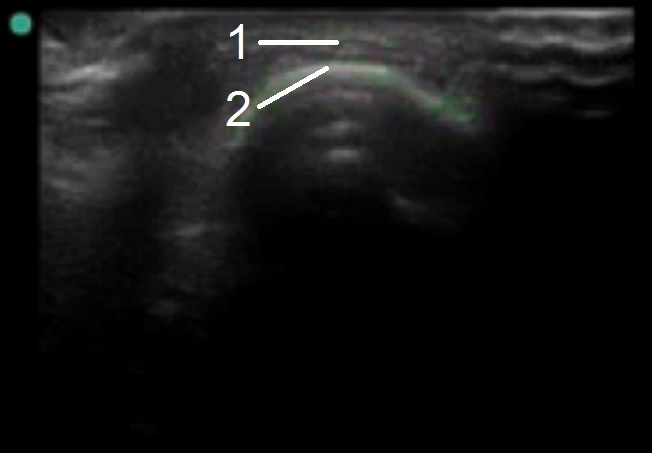

Bild: Fuß und Sprunggelenk, Anatomie des Zehengrundgelenks – kurze Achse

1. Extensorsehne

2. Metatarsaler Kopf